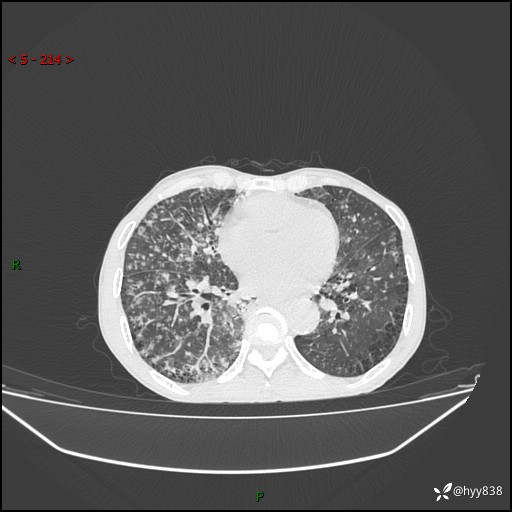

胸部CT平扫